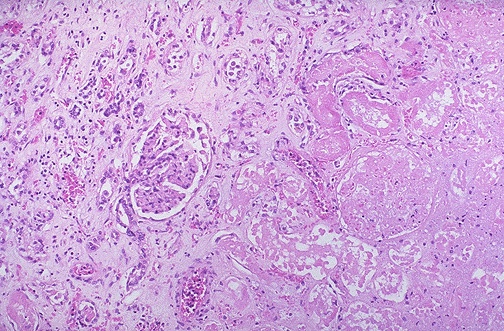

The medium power microscopic appearance of the renal lesion is shown here, with the lesion to the right.